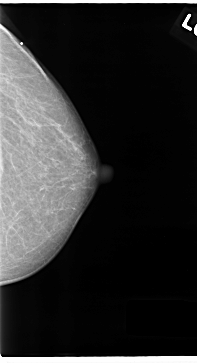

C_0122_1.LEFT_MLO

LEFT_MLO LINES 4704 PIXELS_PER_LINE 2792 BITS_PER_PIXEL 12 RESOLUTION 50 OVERLAY